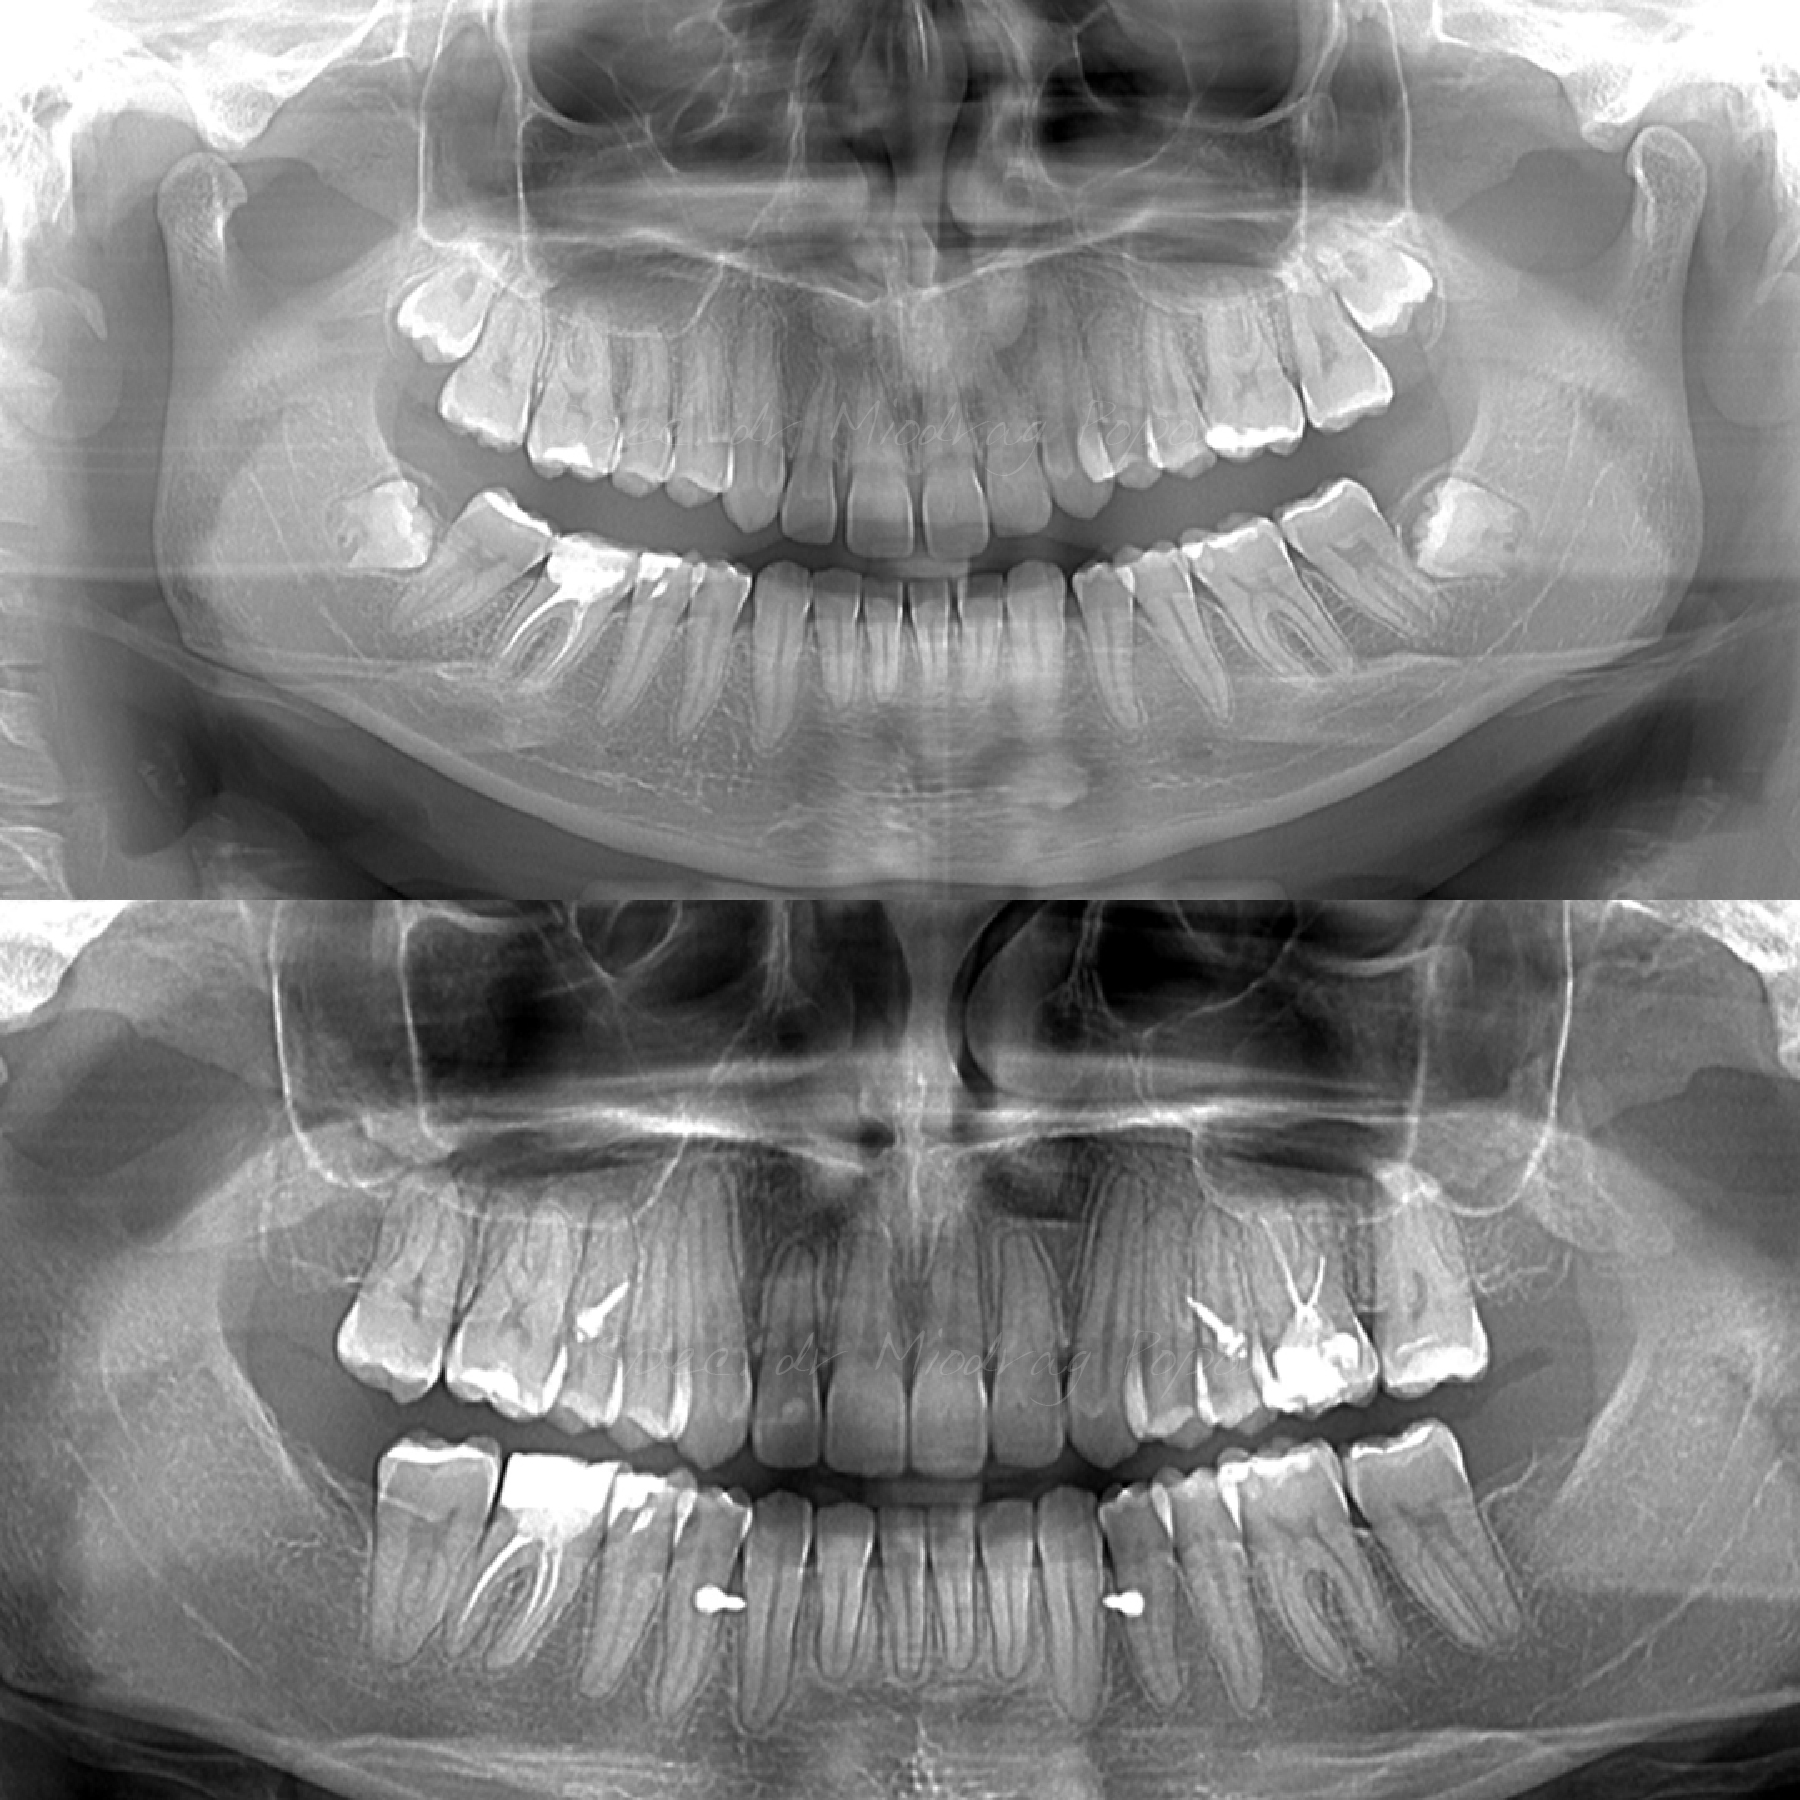

Na početku ortodontske terapije uvek se prvo uspostavilista problema i ciljevi ortodontske terapije na osnovu kojih se pravi mehanički plan.

U ovom slučaju glavni problemi su bili:

- Distalan zagrižaj

- Nagnuta okluzalna ravan

- Asimetričan gummy smile

- Neslaganje sredina zubnih nizova

Svi zajedno smo se trudili i na kraju smo uspeli da dobijemo prelep rezultat.